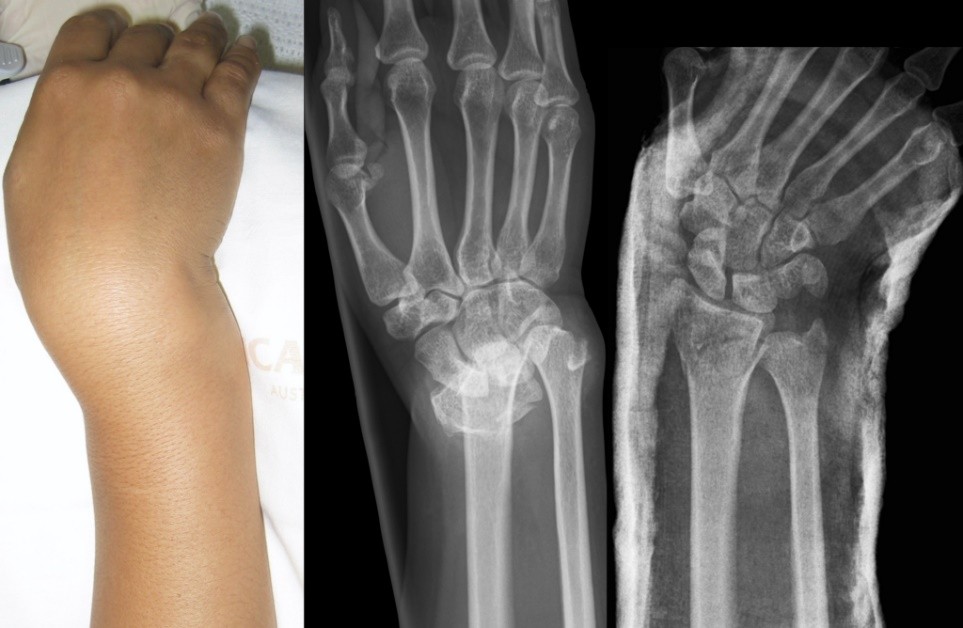

شکستگی مچ دست یکی از شایع ترین شکستگی های انسان است که معمولا در اثر زمین خوردن با کف دست ایجاد می شود. درمان این شکستگی ممکن است شامل جا انداختن دست، گچ گیری، جراحی و فیزیوتراپی باشد. به طور کلی، طول درمان شکستگی مچ دست به شدت و نوع شکستگی، روش درمان و وضعیت سلامت فرد بستگی دارد. اما به طور متوسط، ممکن است ۶ هفته زمان لازم باشد تا استخوان ها دوباره به هم پیوند خورده و گچ حذف شود. پس از حذف گچ، برای بازیابی عملکرد و قدرت مچ دست، نیاز به تمرینات ورزشی و فیزیوتراپی است . معمولا ۳ ماه زمان لازم است تا مچ دست به حالت طبیعی خود برگردد. ما در مجموعه خود برای شما انواع خدمات لازم در منزل را فراهم می کنیم تا دوران بهبود یافتن شکستگی دستتان به بهترین نحو سپری شود.

شکستگی هایی با جابجایی زیاد، چند قطعه ای، یا با در رفتگی مفصل مچ دست نیاز به جراحی و زمان بیشتر برای بهبود دارند.

– کاهش یا از بین رفتن درد و تورم مچ دست، بازگشت حرکت و قدرت مچ دست، عدم وجود تغییر شکل ظاهری یا بد شکلی مچ دست، عدم وجود درد هنگام لمس یا حساسیت در ناحیه شکستگی، عدم وجود کبودی یا رنگ پریدگی در پوست و رادیوگرافی ساده که نشان دهنده جوش خوردن استخوان ها و عدم جابجایی آنها باشد.

– شکستگی های بدون جابجایی استخوان، یعنی آن هایی که استخوان ها در محل اصلی خود باقی مانده اند، معمولاً با گچ گیری و بیحرکت نگه داشتن مچ دست درمان می شوند. این روش درمان ساده و ارزان است و عوارض جراحی را ندارد. طول زمان لازم برای بهبودی با این روش حدود ۶ هفته است.

– شکستگی های همراه با جابجایی استخوان، یعنی آن هایی که استخوان ها از محل اصلی خود منحرف شده اند، معمولاً نیاز به جراحی دارند تا استخوان ها را تراز کرده و با پلات و پیچ جراحی ثابت نگه دارند. این روش درمان پیچیده و گران است و خطر عفونت، التهاب، خون رسانی نامناسب و عدم تطابق استخوان ها را دارد.